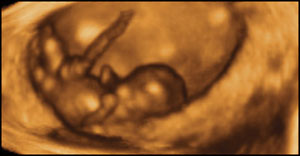

“I became active in the pro-choice movement (first as a legislative worker, then as a clinic escort). I suppose in retrospect I was trying to justify what I had done. Then in 1991 I became pregnant with my son. I went for prenatal visits and was horrified to see a real baby on the Ultrasound screen, and also to hear his heartbeat on the Doptone device! I had not realized the heartbeat started so soon; they never told me anything about that at Planned Parenthood, when my parents brought me for the abortion.”

The heart starts beating around 21 days.